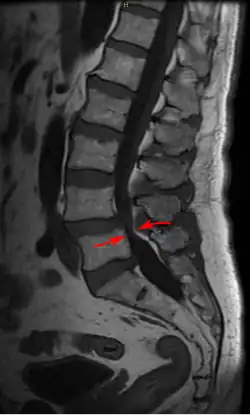

| Lumbar vertebra showing central stenosis and lateral recess stenosis. | |

Spinal stenosis may be congenital (rarely) or acquired (degenerative), overlapping changes normally seen in the aging spine.[6][7] Stenosis can occur as either central stenosis (the narrowing of the entire canal) or foraminal stenosis (the narrowing of the foramen through which the nerve root exits the spinal canal). Severe narrowing of the lateral portion of the canal is called lateral recess stenosis. The ligamentum flavum (yellow ligament), an important structural component intimately adjacent to the posterior portion of the dural sac (nerve sac) can become thickened and cause stenosis. The articular facets, also in the posterior portion of the bony spine can become thickened and enlarged, causing stenosis. These changes are often called "trophic changes" or "facet trophism" in radiology reports. As the canal becomes smaller, resembling a triangular shape, it is called a "trefoil" canal.

The normal lumbar central canal has a midsagittal diameter (front to back) greater than 13 mm, with an area of 1.45 cm2. Relative stenosis is said to exist when the anterior-posterior canal diameter measures between 10 and 13 mm. Absolute stenosis of the lumbar canal exists anatomically when the anterior-posterior measurement is 10 mm or less.[12][13][14]